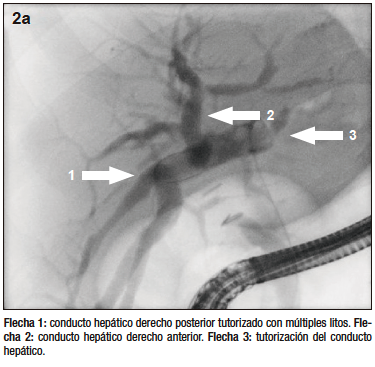

Figura 2a. Colangiopancreatografía retrógrada endoscópica

El estudio por colangioresonancia evidenció una variante anatómica biliar tipo 3 de la clasificación de Huang, ya que el conducto hepático posterior derecho drenaba en el conducto hepático izquierdo.1 Se observaron imágenes compatibles con litiasis intrahepática derecha y litiasis en el colédoco distal. La CPRE confirmó la presencia de la variante anatómica del patrón ductal hepático derecho y permitió realizar una canulación selectiva con posterior extracción de litos mediante balón y canastilla.2 El paciente tuvo una buena evolución clínica sin complicaciones.